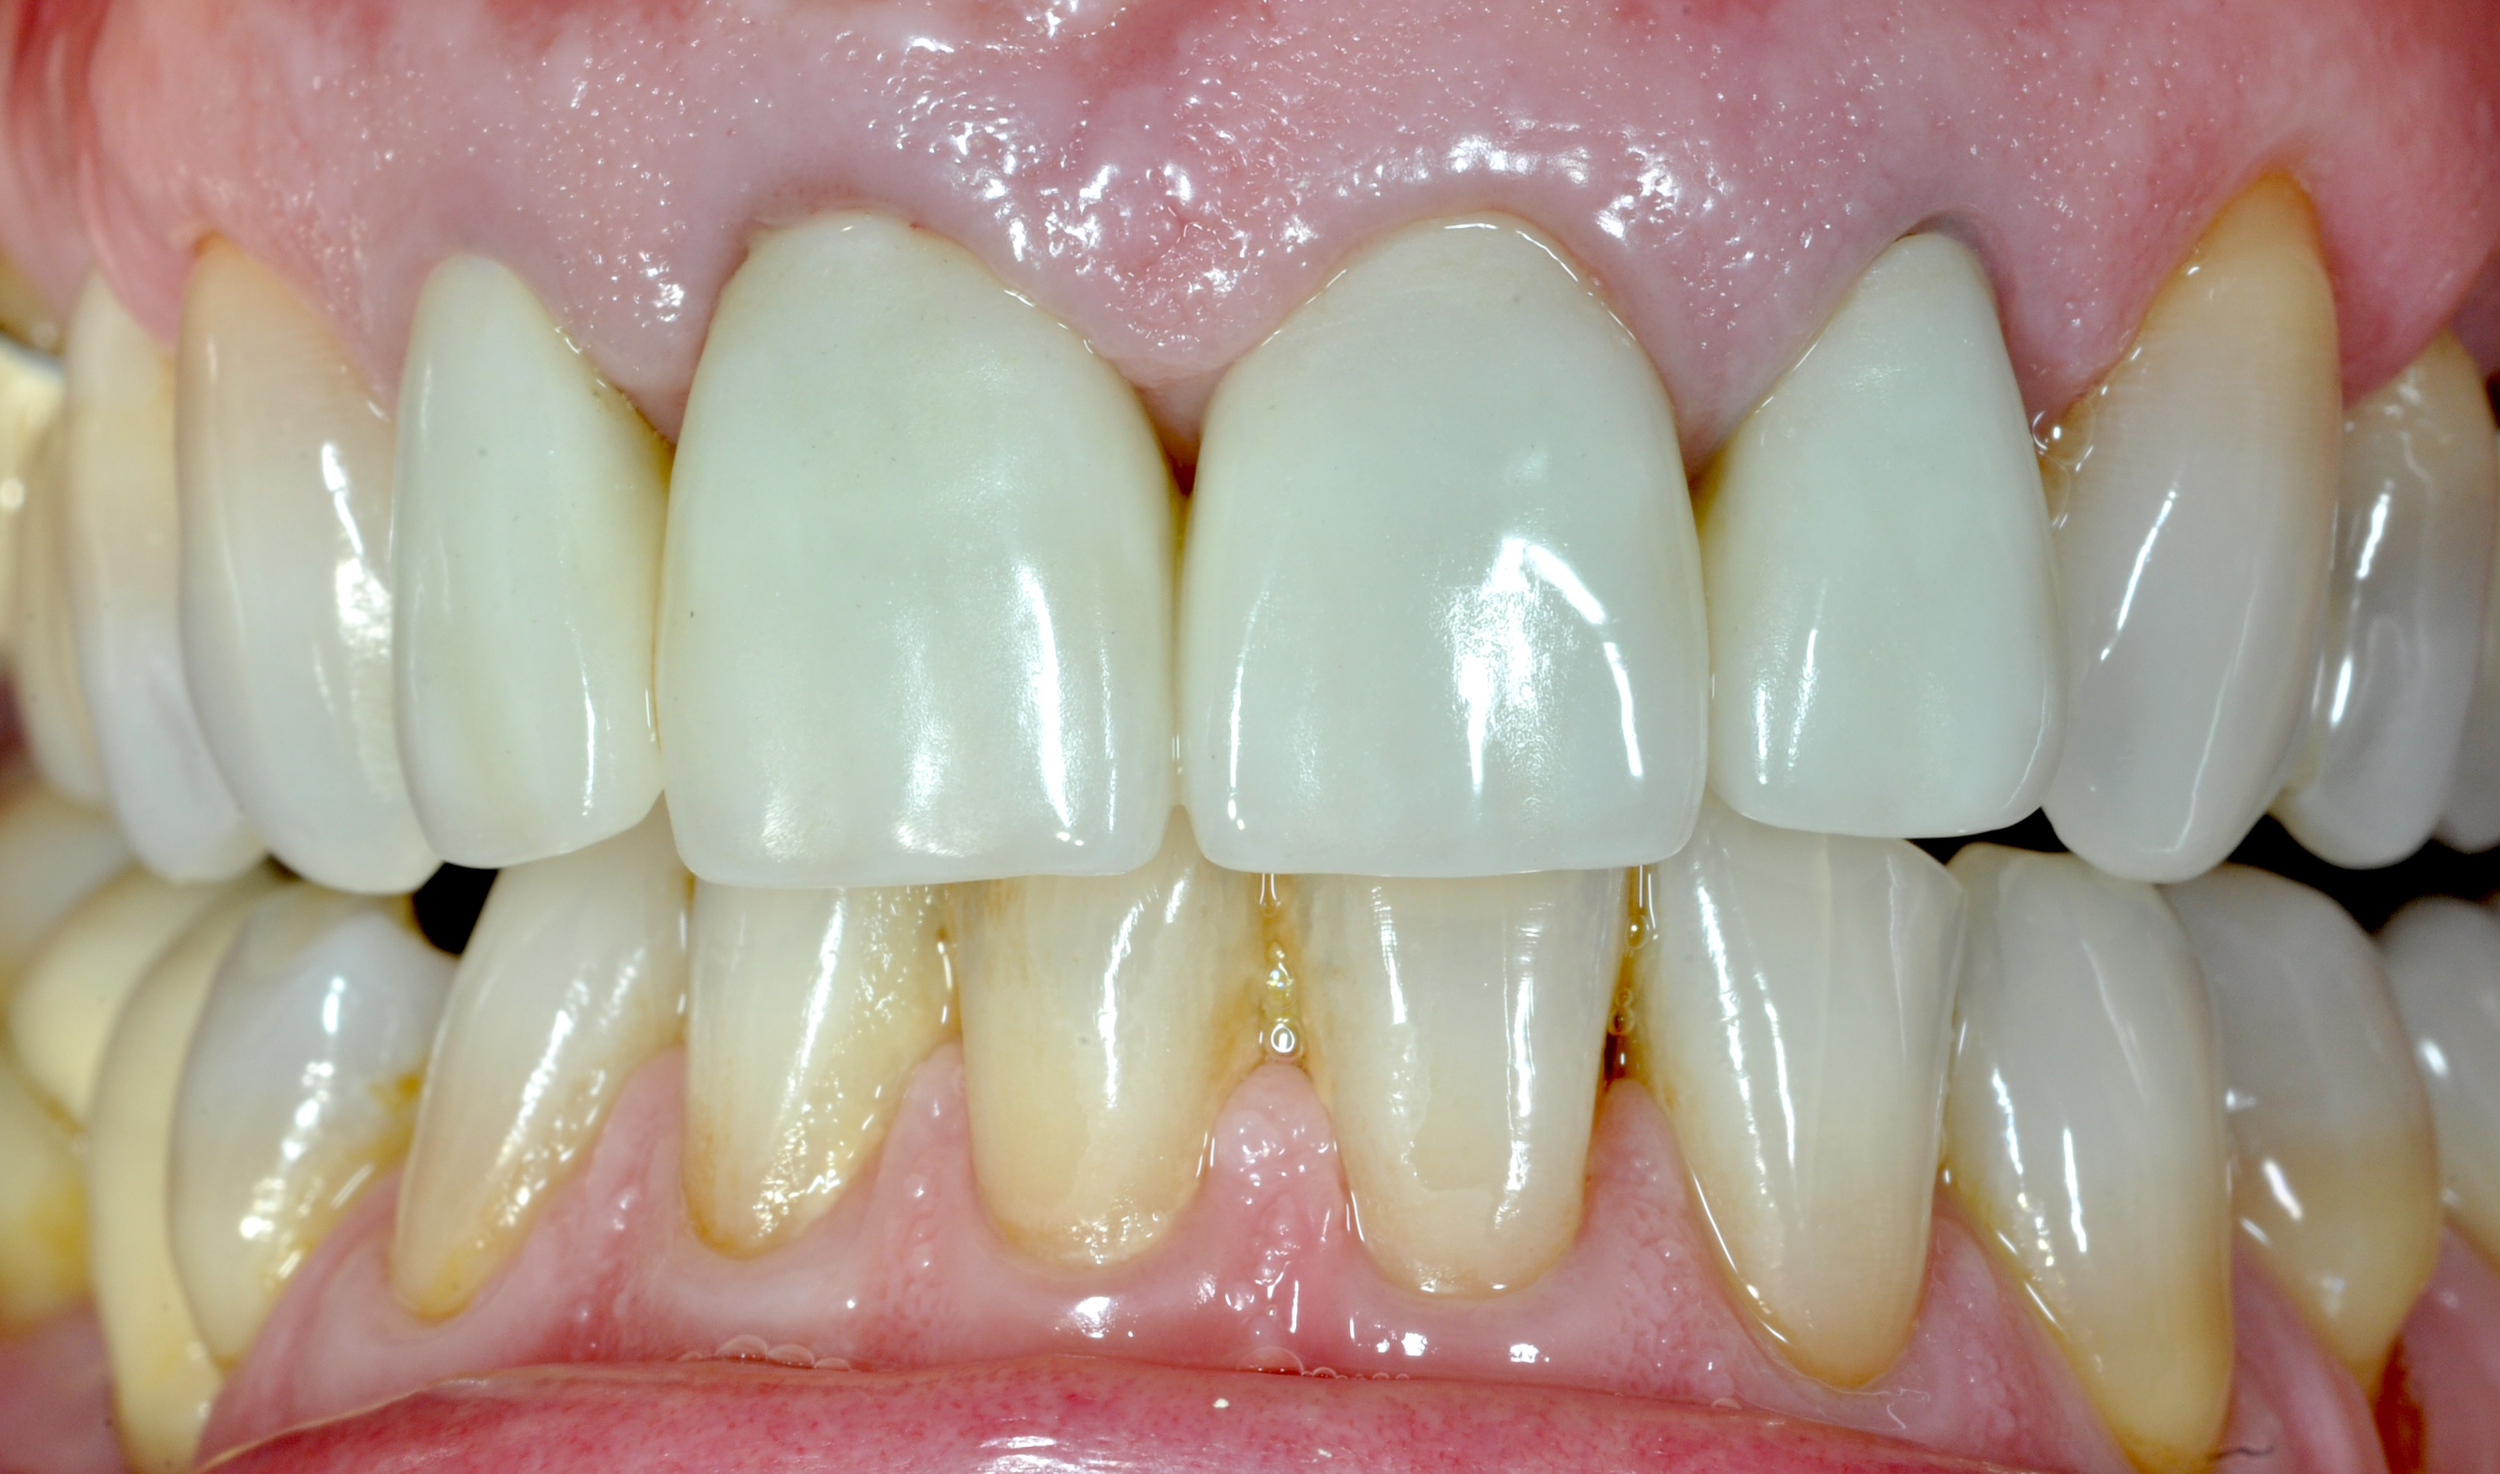

Caso 1

La paziente ha subito un trauma sugli elementi frontali nel 2000. I denti sono stati recuperati e riabilitati protesicamente con corone fisse sulle radici naturali. Dopo più di 20 anni, l’elemento 11 mostra segni di riassorbimento radicolare (tipico dei denti traumatizzati). Si procede con la sostituzione dell’elemento con un impianto singolo.

DOPO